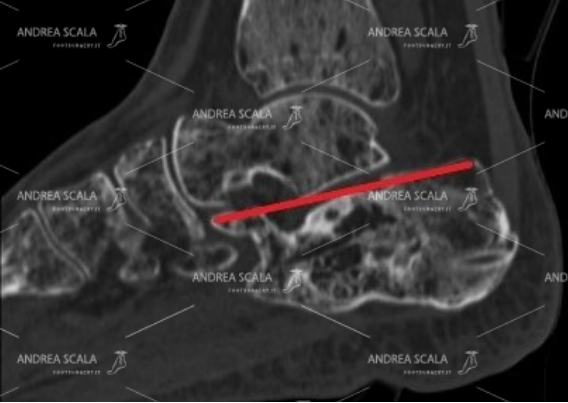

La Radiografia del piede fratturato è importante per mostrare che il calcagno non è normale, ma non è sufficiente. Quando si sospetta la frattura del calcagno occorre fare la TAC. La TAC mostra con precisione che dopo la frattura il calcagno è schiacciato, l’angolo di Bohler è appiattito, l’articolazione è spezzata, si vedono bene i frammenti della frattura.

La Radiografia non è sufficiente per capire la gravità della frattura del calcagno. E’ necessario fare la TAC. Dopo la frattura il calcagno è schiacciato, l’angolo di Bohler è appiattito, l’articolazione è spezzata, si vedono bene i frammenti della frattura.

La TAC eseguita dopo l’intervento con i fili di acciaio fa vedere molto bene che il calcagno è rimasto schiacciato. L’angolo di Bohler non è stato ricostruito. L’articolazione è rimasta infossata come il giorno dell’incidente.